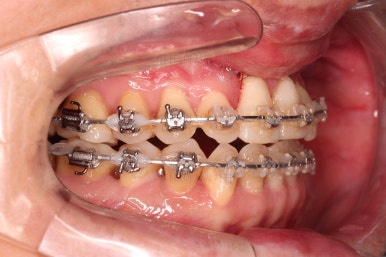

부산구순구개열교정 키다리아저씨치과에 처음 내원하셨을 당시의 입안의 모습입니다.

구순구개열 환자분의 일반적인 입 안의 특징은 다음과 같습니다.

골 결손부위의 치아 결손이 빈번하다.

구개열 봉합술을 어린 나아이에 받기 때문에, 해당 부위의 상흔이 남는다.

상흔의 영향으로(피부 상처도 일반 피부 보다는 상처가 아문 부위가 더 단단하죠.) 입천장의 잇몸이 굉장히 단단하다.

그래서 가로폭의 성장이 잘 되지 못하여 악궁(치아가 배열된 U자 형태)이 협착된 경우가 많다.

공간 부족으로 치열이 매우 삐뚠 경우가 많다.

공간 부족과 악궁 형태 등으로 인해 부정교합이 함께 나타난다.

골 결손부위 근처의 치아는 뼈가 약한 경우가 많아 튼튼하지 못하고 만지면 흔들리는 경우가 많다.

이번 환자분도 이와 같은 일반적인 특징이 그대로 나타나 있었습니다.

양측성 구순구개열이었으므로 작은 앞니(대문니와 송곳니 사이)가 양쪽 다 결손이었고, 또 다른 이유로 아래 앞니도 1개 없는 상태였습니다.

위아래 장치를 부착했습니다.

2019년부터는 구순구개열 환자분들의 교정치료에 건강보험이 적용되어서 비용적인 측면에서 혜택이 생겼는데요. 아쉽게도 아직은 투명교정장치는 적용이 안되고, 브라켓-철사 교정장치만 적용이 되긴 합니다.